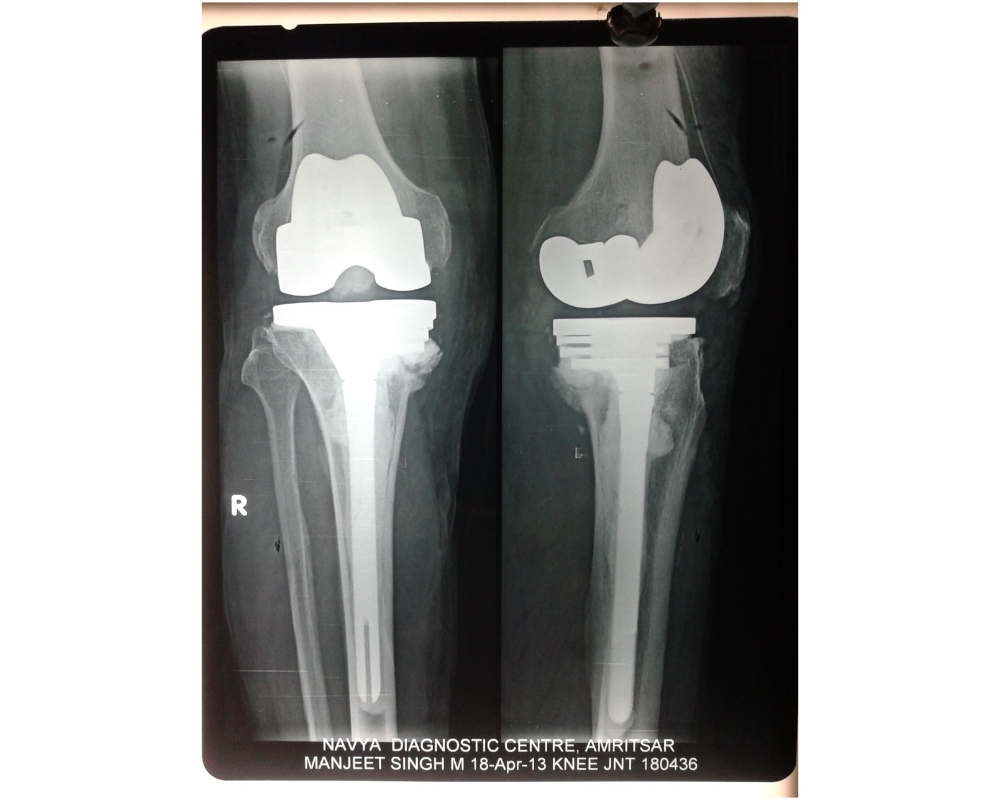

El diseño innovador y patentado de este implante ortopédico le brinda la máxima flexibilidad para cumplir con prácticamente cualquier tamaño y forma de rodilla. Sus aumentos reversibles y apilables le permiten hacer coincidir las deficiencias óseas reemplazadas con precisión, mientras que su placa base de bajo perfil conserva la mayor cantidad de hueso posible.

Basándose en el éxito clínico de la prótesis de rodilla Freedom Knee de Maxx Orthopedics , el sistema de revisión de rodilla Freedom PCK promueve un tamaño y una forma óptimos para replicar tanto la anatomía femoral como la cinemática normal de la rodilla.

- La placa base tibial de bajo perfil y que conserva el hueso permite corregir casos de baja densidad ósea o deformidades graves.

- Los aumentos reversibles y apilables permiten una adaptación superior a las deficiencias óseas reemplazadas.